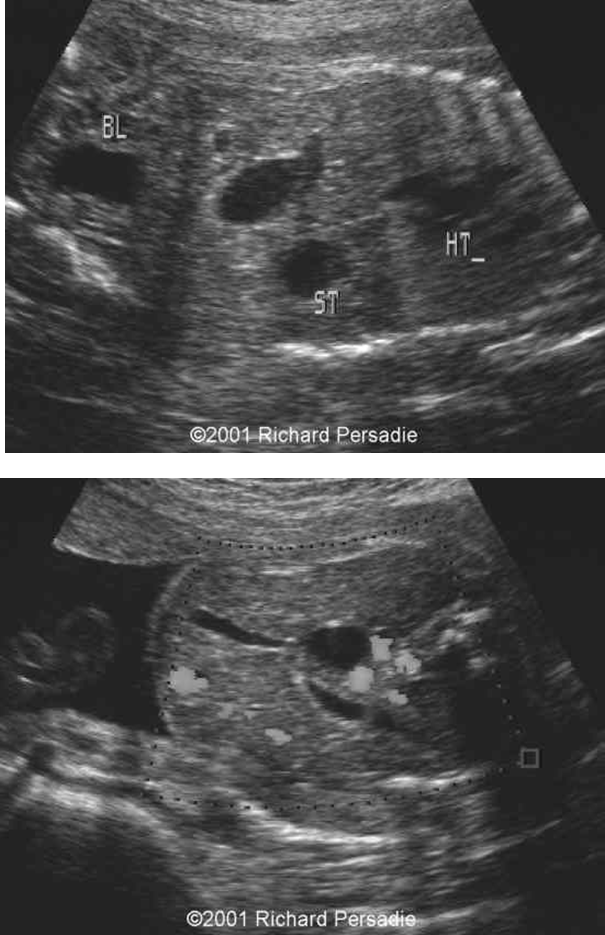

What is this image showing?

Partial situs- stomach on right and hypoplastic left heart